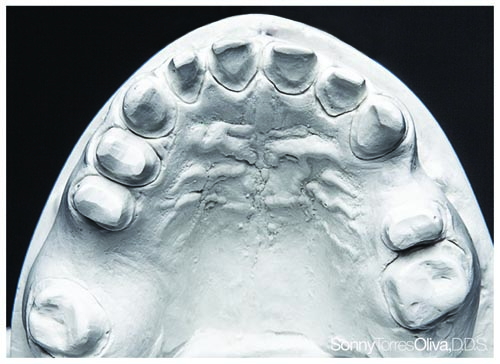

Fig. 7: Palatal view of the maxillary arch revealing the distal/lingual (DL) composite restorations on teeth #9 and #11.

Tools